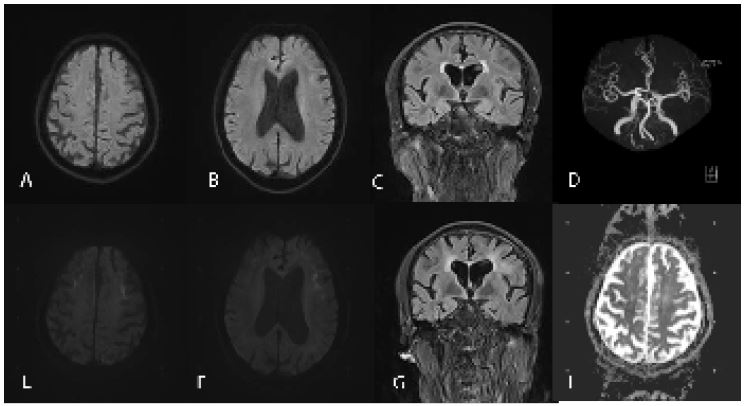

Case 2: A 63-year-old retired farmer with a primary school education presented to our hospital because of episodic dizziness and mental disorders for 5 years in June 16, 2022. On May 1, 2017, the patient initially presented with paroxysmal dizziness, which lasted several to more than 10 minutes each time, accompanied by a sense of rotation. After the last attack, he experienced mental abnormalities, cognitive impairment, lethargy, occasional nonsense. During these attacks, the patient denied epilepsy, muscle weakness. Brian MRI showed multiple strip like high-intensity signals in bilateral frontal parietal lobe, corpus callosum, and near the posterior horn of lateral ventricle on DWI, while equal signals on ADC. The ventricular system was enlarged and the sulci fissure widened, which was considered as reversible posterior leukoencephalopathy syndrome (Figures 3A-D). After treatment with antiplatelet and lipid-lowering drugs, the patient’s symptoms improved after 3 days. On April 1, 2020, the patient experienced paroxysmal dizziness again, accompanied by a sense of rotation and unstable walking. The dizziness was not related to posture or activity, and there was no numbness, muscle weakness, or mental abnormality. Brian MRI showed that bilateral subcortical high-intensity signals in the frontal and parietal lobes were enhanced compared to before, and the lesion area was enlarged (Figures 3E-H). The above treatment was given again and the symptoms improved after 1 week. On June 16, 2022, the patient experienced mental and behavioral abnormalities, characterized by walking barefoot, inability to recognize family members, frequent yawning, inability to avoid obstacles, inability to communicate, occasional self talk, accompanied by high fever, no muscle weakness, consciousness disorders, or seizures. He had a medical history of «type 2 diabetes, neurogenic bladder associated with diabetes, hypertension, coronary heart disease». Family history is negative.

Neurologic examination demonstrated lethargy, speech disturbance, cognitive impairment, miosis, bilateral Babinski sign positive. Mini-Mental State Examination was 17, Frontal Assessment Battery score was 10. Blood tests were normal apart from hypokalemia of 3.18 mmol/L ((3.5-5.5), hyperlactatemia of 4.56 mmo/L (0.5-2.2) and a mildly elevated neutrophils count of 7.85 x 109/L (1.8-6.3). Procalcitonin was 0.l ng/ml (0-0.06). Urinary tests showed increased protein levels, white blood cell counts, red blood cell counts and bacterial counts. Urine organic acid analysis, amino acid and acylcarnitine spectrum analysis of genetic metabolic disease were within normal limits. Brain MRI showed that the lesion area was enlarged again compared with the previous imaging (Figures 3I-L). Urinary ultrasound showed that the residual urine volume in the bladder is about 40 ml, and there is no obvious abnormality in both kidneys, ureters, or bladder. Electroencephalogram showed no epileptic discharge. NCS showed that Sensory Nerve Action Potentials (SNAP) were decreased in bilateral median nerve, superficial peroneal nerve and sural nerve. Distal Motor Latency (DML) were prolonged in bilateral median nerve. Motor Nerve Conduction Velocity (MNCV) were decreased in bilateral median nerve, tibial nerve, common peroneal nerve and left ulnar nerve. Compound Motor Action Potential (CMAP) were decreased in bilateral common peroneal nerve. The latency of F-wave was prolonged in bilateral tibial nerve. SSR showed abnormalities in both lower limbs. A histopathological examination of skin biopsy specimens showed eosinophilic hyaline intranuclear inclusions in the sweat gland, adipocytes, and spindle cells of the skin tissue (Figures 4 A,B). Additionally, an expansion of 108 GGC repeated in the 5 ‘UTR of the NOTCH2NLC gene was detected by repeat-primed polymerase chain reaction (Figure 4C), further confirming the diagnosis of NIID. After 6 months, she still experienced intermittent dizziness, but no further episodes of mental abnormalities by telephone follow-up.

Figure 3: (H) findings. DWI shows multiple strip like high-intensity signals in the corticomedullary junction of the bilateral frontal parietal lobe, corpus callosum, and near the posterior horn of lateral ventricle (A,B). FLAIR shows diffuse high-intensity signal of white matter (C). MRA shows no significant intracranial aortic stenosis or occlusion (D). DWI shows that bilateral subcortical high-intensity signals were enhanced compared to before, and the lesion area was enlarged (E-G). DWI shows the lesion area was enlarged again (I-K).

Figure 4: Histopathological and genetic analyses. Hematoxylin-eosin staining shows eosinophilic inclusion bodies in the sweat gland, adipocytes, and spindle cells (A,B). The inclusions immunopositive to p62 antibody (C). RP-PCR of the patient with a characteristic saw-tooth pattern for an expansion of 108 GGC repeated in the 5′ -untranslated region of the NOTCH2NLC Gene (D). RP-PCR, repeat-primed PCR.